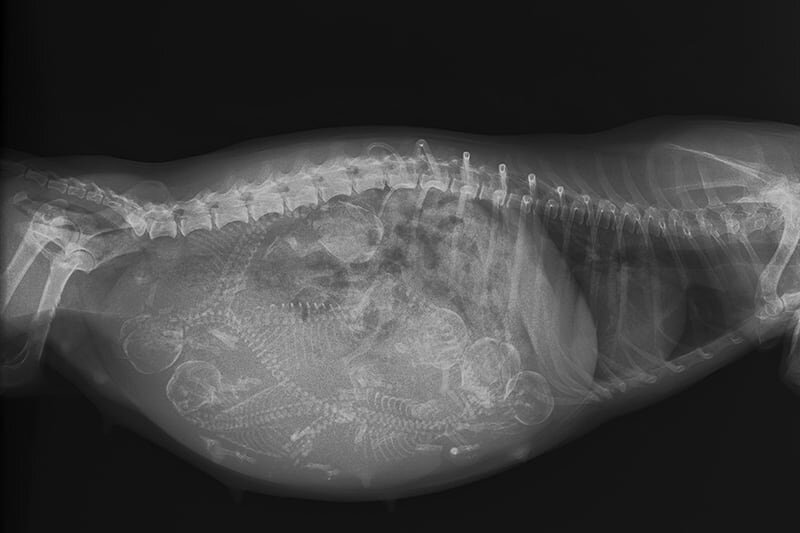

Рентген

Цифровые рентгеновские лучи выделяют очень небольшое количество радиации и считаются безопасными для беременных собак. Рентген также может быть эффективным способом выявления беременности у собак, когда у них по крайней мере 42 недели беременности. На 55 неделе ваш ветеринар может определить, сколько плодов присутствует, и предоставить вам приблизительную дату, когда вы должны ожидать рождения щенков. Это особенно полезно, если вашей собаке предстоит плановое кесарево сечение.

Лучший момент для проведения рентгена на 55/56 день, чтобы определить размер и количество щенков. Рентген можно сделать раньше, но позже он даст вам больше информации о размере щенка, и знание того, что последний щенок вышел, успокаивает. Это также может помочь узнать, что все щенки выглядят здоровыми. Рентген может показать крупного щенка, и тогда можно ожидать трудных родов и вызвать ветеринара по вызову. (Он должен быть на вызове в любом случае, так как вы никогда не знаете, какие проблемы могут возникнуть, например, эти большие щенки застревают в родовых путях.) Чтобы помочь щенку двигаться, осторожно обхватите щенка чистым сухим полотенцем, слегка поверните его из стороны в сторону, а затем, когда у матери произойдет сокращение, плавно потяните вниз и через живот матери к ее голове.